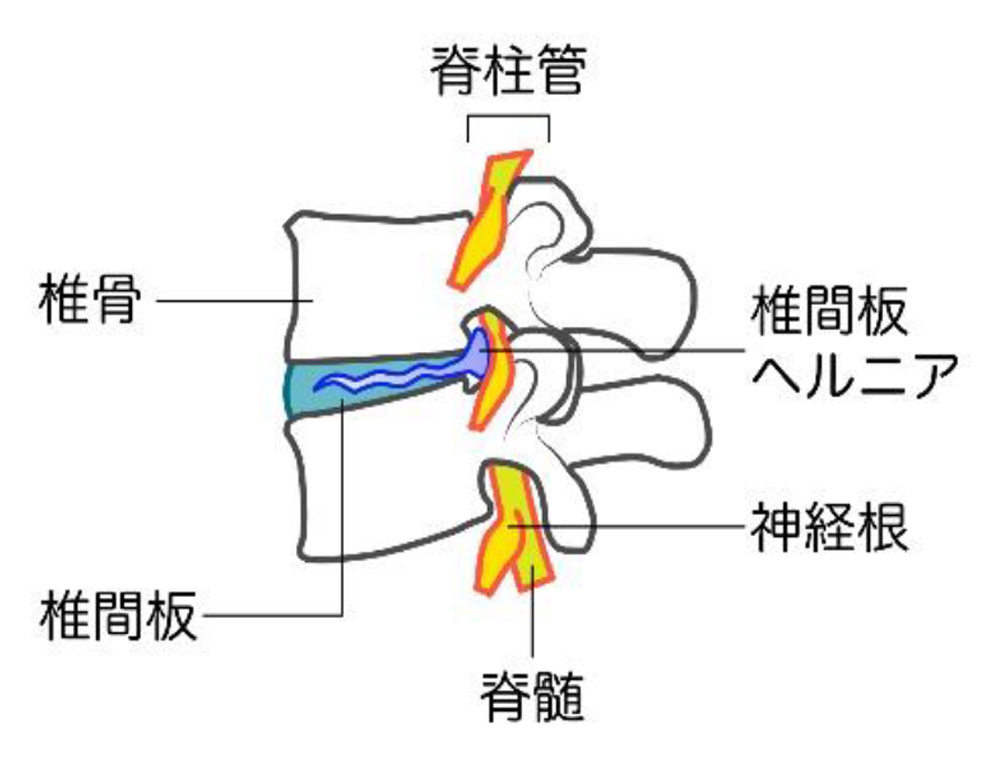

さらに椎骨と椎骨との間には椎間板という組織があり、椎骨にかかる衝撃を和らげるクッションのような役割を果たしています。

加齢による椎間板の変性が進み、骨がとげ状に大きくなって骨棘を形成することや、靭帯が厚く硬くなることで脊柱管にある脊髄が圧迫され、四肢に痛み、しびれが出る疾患です。

■頸椎椎間板ヘルニア

頸椎を構成する椎骨と椎骨の間には椎間板というクッション性のある組織が存在します。何らかの原因でその椎間板が飛び出し、神経を圧迫するのが椎間板ヘルニアです。

■頚部脊柱管狭窄症

主に加齢に伴う椎間板の変性により、劣化・膨隆・突出、黄色靭帯の肥厚が原因となり、それらによって脊髄や神経根が脊柱管を狭窄します。その結果、神経の血流が低下して神経障害を起こした状態をいいます。